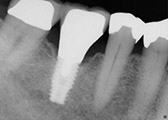

We are proud to offer dental implants for our patients. Dental implants are roots placed in your mouth for either permanent teeth to be placed on or ones that you can remove.